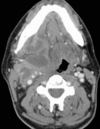

6

Q

A

Otitis externa difusa

( Aspirar secreción + ATB per gotas )